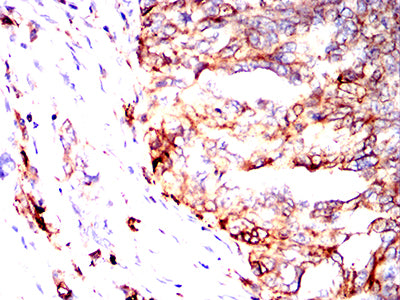

| IHC | 1/50-1/100 | Human,Mouse,Rat |

The MonoMethyl-p53 (Lys370) antibody is widely employed in cancer research to study p53 regulation in tumorigenesis, particularly in cancers with wild-type p53. It enables detection of this modification via techniques like Western blotting, immunohistochemistry, and immunoprecipitation, aiding investigations into p53's functional dynamics in cell lines, tissues, or patient samples. Studies using this antibody have provided insights into how Lys370 methylation affects p53-mediated tumor suppression, its crosstalk with other modifications (e.g., phosphorylation, acetylation), and its potential as a biomarker or therapeutic target. Researchers frequently apply it in models of colorectal, breast, and lung cancers to explore context-specific regulatory mechanisms. Proper validation with methylation-deficient mutants or enzymatic treatments is essential to ensure specificity in experimental settings.